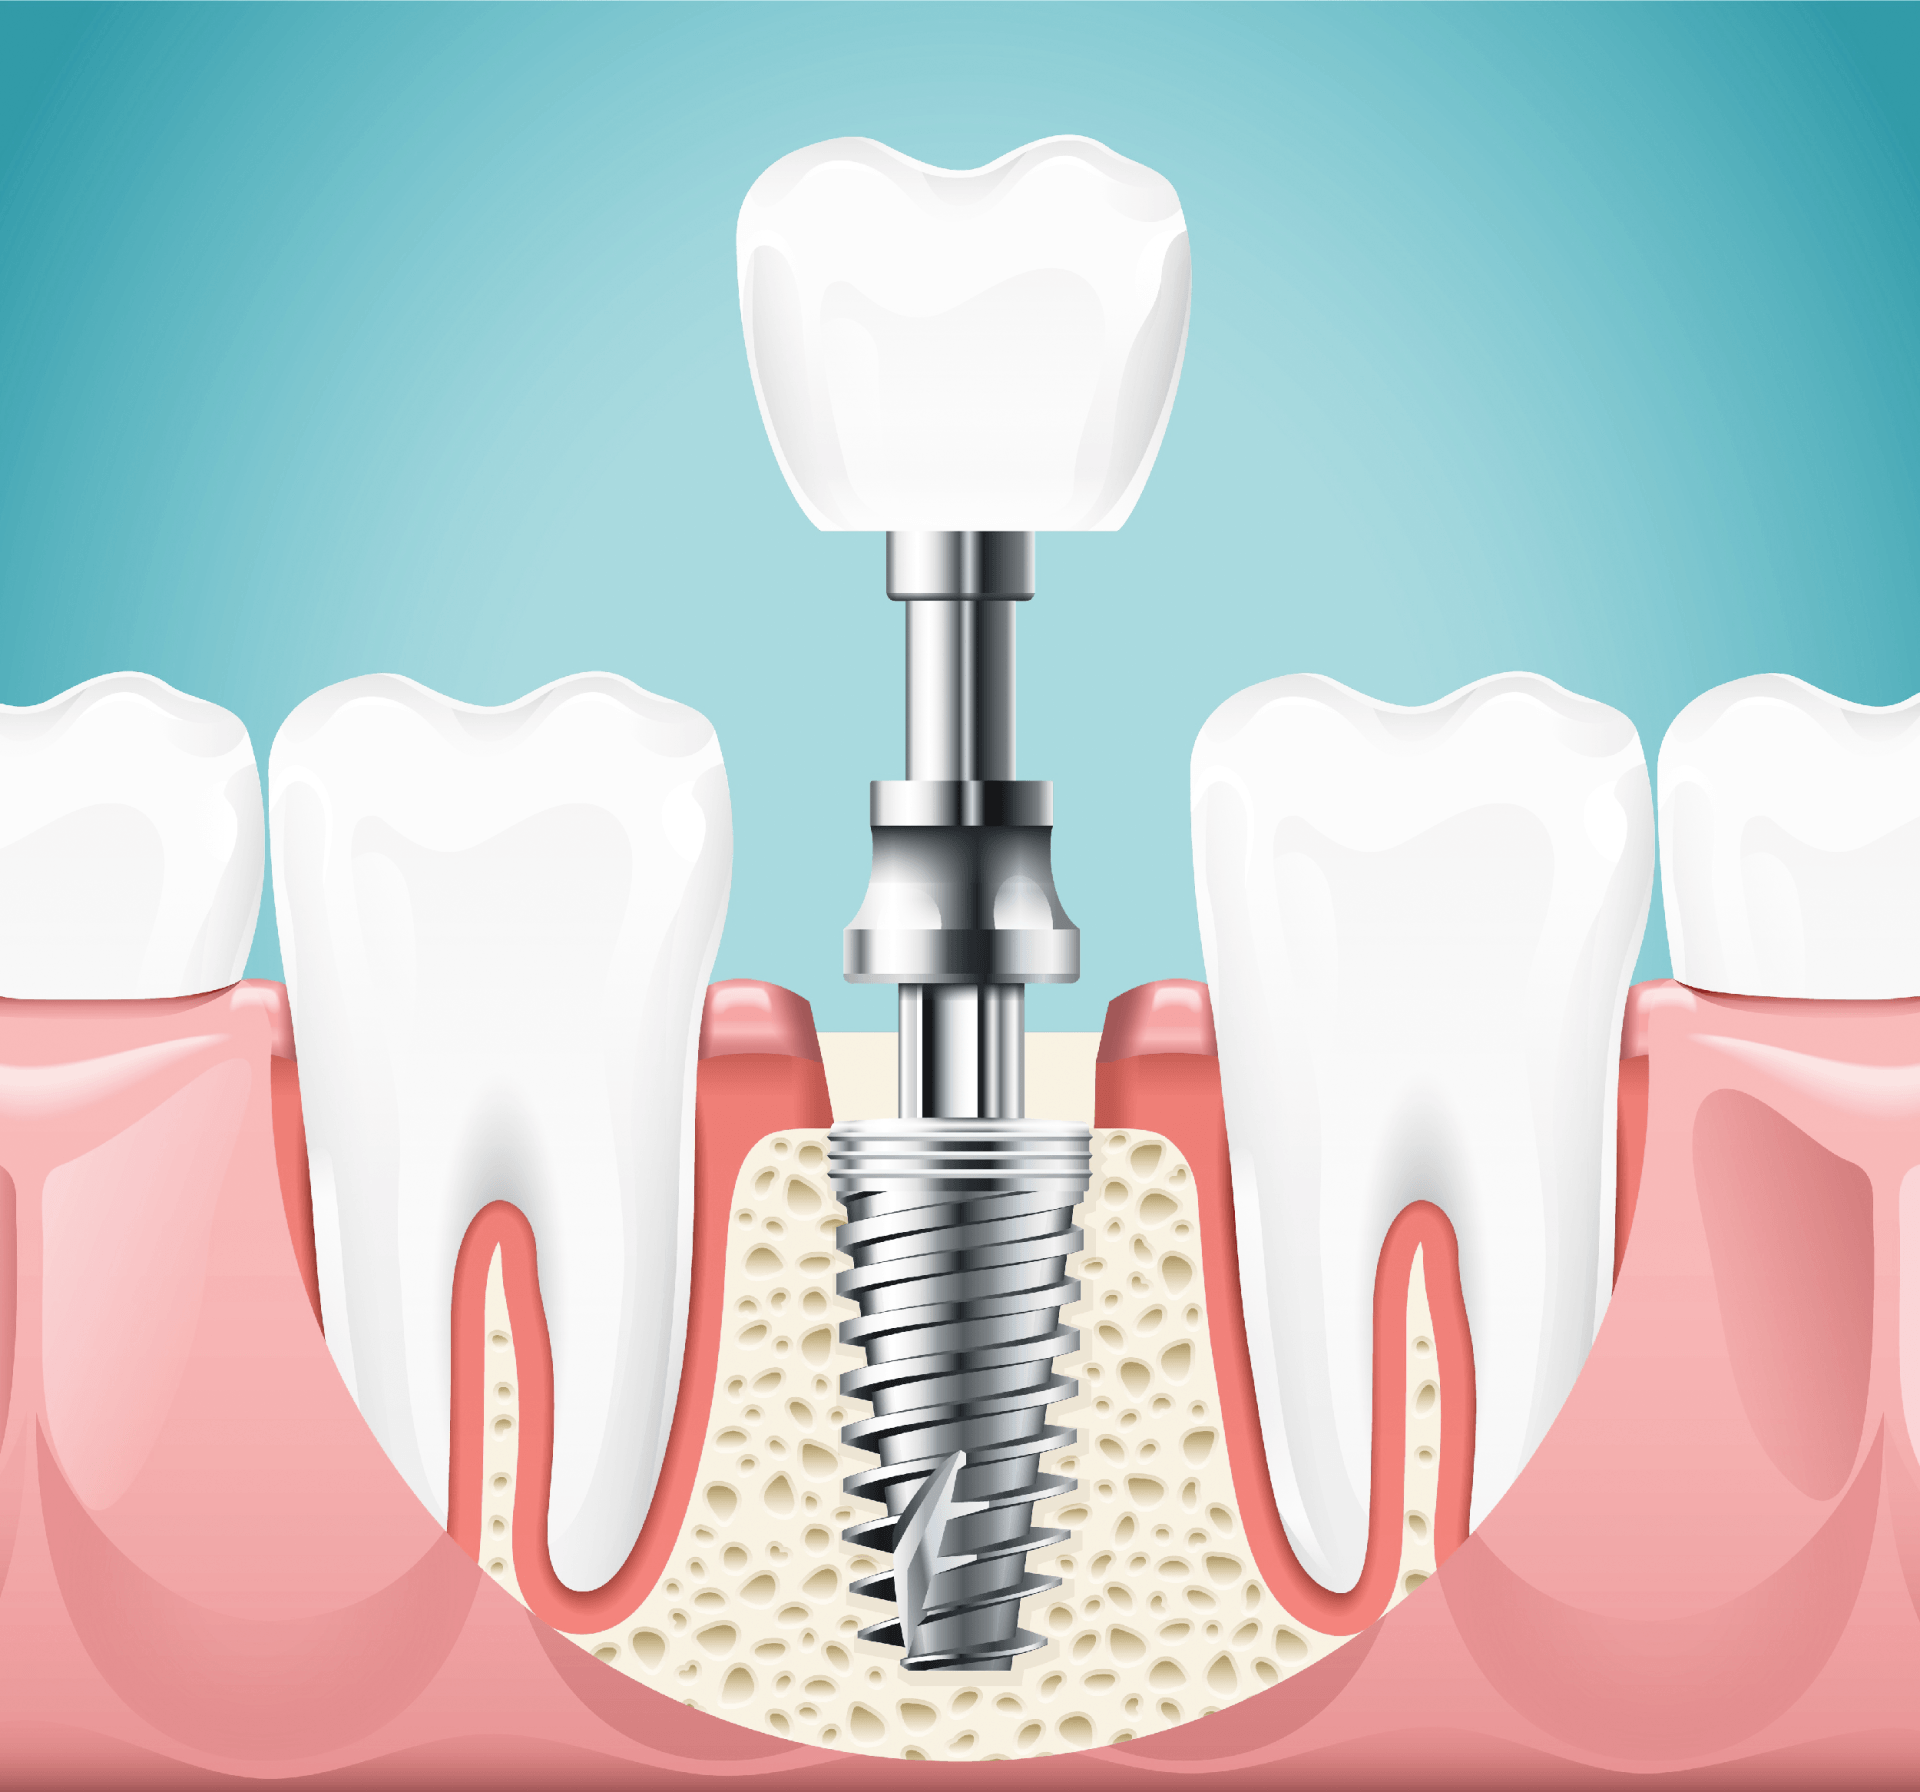

Quando si parla di impianto dentale si fa riferimento ad una piccola vite realizzata per lo più in titanio, utilizzata con lo scopo di andare a sostituire la radice del dente naturale che per vari motivi è venuto a mancare. Generalmente, i classici impianti dentali sono formati da tre elementi:

1- La vite endossea: svolge la funzione della radice del dente; ne esistono di diverse forme, fogge e lunghezze. È il clinico che decide quelle più adatte per il caso specifico.

2- L’abutment: ha la funzione di unire la vite in titanio con l’elemento che si sovrappone (dente o protesi); anche in questo caso sono numerosi tipi e modelli da scegliere con accuratezza.

3- La protesi dentaria: indica la parte utilizzata per sostituire il dente perso. Come la vite, anche la protesi può essere realizzata in vari materiali come ceramica o resina. La cosa più complessa di questa parte è la ricerca dell’armonia di forme e colori salvaguardando la funzione masticatoria.